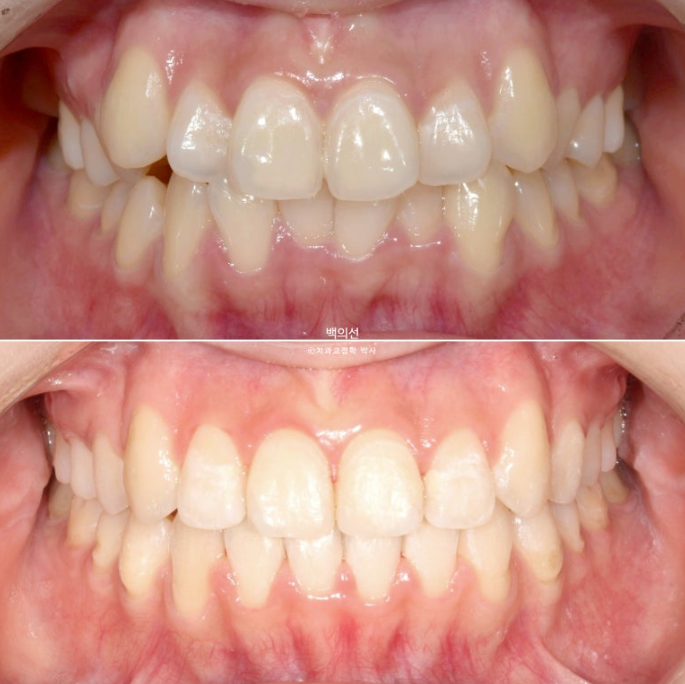

이제 전후 비교 보겠습니다.

인비절라인으로 치료를 시도했던 기간은 1년 3개월(그중에 7개월은 장기 미내원), 클리피씨 장치를 붙여 치료한 기간은 11개월 입니다.

23.05~25.07

교정을 하면 얼굴이 갸름해집니다.

웃는 사진 보겠습니다.

돌아가있던 송곳니 덧니가 해소가 되며 입동굴이 시원하게 생겼습니다.

깔끔해진 미소